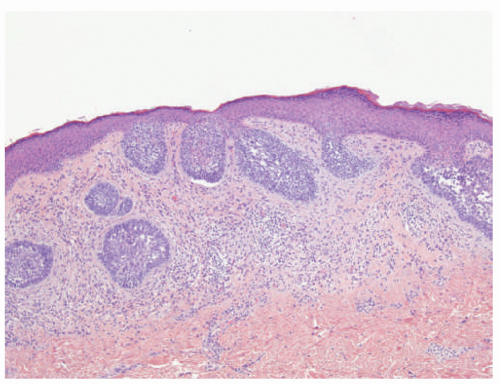

![]() FIGURE 23-9. White sponge nevus displays parakeratosis, acanthosis, and prominent clearing of suprabasal keratinocytes. |